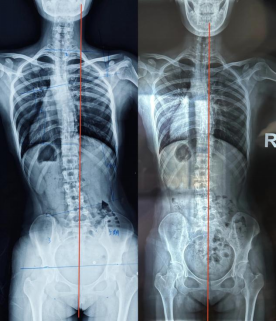

脊柱侧弯-体态矫正(二)

脊柱侧弯-体态矫正